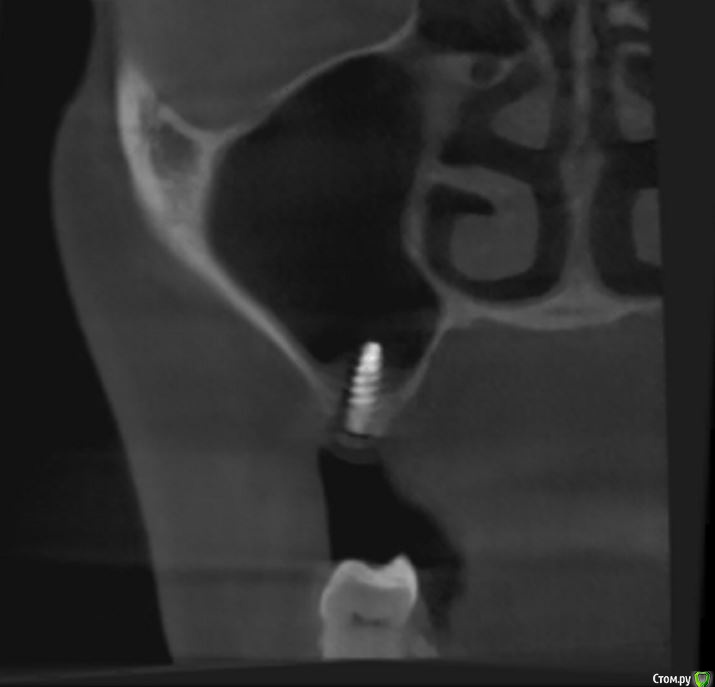

jm3300 Опубликовано 12 июля, 2016 Автор Поделиться Опубликовано 12 июля, 2016 А до операции КТ могли бы выложить? И сколько времени отсутствовали зубы в этой области?отсутствовали достаточно долги. КТ до: Ссылка на комментарий

jm3300 Опубликовано 14 июля, 2016 Автор Поделиться Опубликовано 14 июля, 2016 выкладываю кт Ссылка на комментарий

умножающий печаль Опубликовано 14 июля, 2016 Поделиться Опубликовано 14 июля, 2016 Промыть пазуху через соустье, курсом. Я отправляю к ЛОРам. Антибиотикотерапия, гипосенсибилизация. Один из винтов вестибулярно без костной поддержки, на мой взгляд. 1 Ссылка на комментарий

red_butler Опубликовано 15 июля, 2016 Поделиться Опубликовано 15 июля, 2016 гайморит всё таки есть?Не увидел, один винт похоже на выход 1 Ссылка на комментарий

syrovovec Опубликовано 15 июля, 2016 Поделиться Опубликовано 15 июля, 2016 (изменено) Пазуха чистая, Антон, какой винт на выход не понял?Может у пац аллергия ? Изменено 15 июля, 2016 пользователем syrovovec 1 Ссылка на комментарий

kladoffka Опубликовано 15 июля, 2016 Поделиться Опубликовано 15 июля, 2016 Тоже не понял, вроде все хорошо стоят. Главное слизистые то в покое. 1 Ссылка на комментарий

red_butler Опубликовано 15 июля, 2016 Поделиться Опубликовано 15 июля, 2016 Пазуха чистая, Антон, какой винт на выход не понял?Может у пац аллергия ?На последних срезах, вестибулярно на 2/3 кости нет.Какая уж аллергия, если боль и отек 1 Ссылка на комментарий

умножающий печаль Опубликовано 15 июля, 2016 Поделиться Опубликовано 15 июля, 2016 (изменено) гайморит всё таки есть?Судя по симптоматике, которую вы представили, есть. На снимке признаки могут запаздывать, ежели процесс острый, хотя снижение пневматизации должно быть заметно. Я на мониторе не разглядел. Рентген всего лишь доп. метод обследования. Диагноз ставит врач, то есть вы, сопоставив клинику и доп.методы.З.Ы. Я не думаю, что в вашем случае причина гайморита имплантация. Временной интервал слишком велик. Изменено 15 июля, 2016 пользователем умножающий печаль 1 Ссылка на комментарий

умножающий печаль Опубликовано 15 июля, 2016 Поделиться Опубликовано 15 июля, 2016 Тоже не понял, вроде все хорошо стоят. Главное слизистые то в покое.Это пока в покое. Винт не покрытый костью, долго под мягкими тканями оставаться не будет. Неизбежна рецессия со всеми вытекающими. 1 Ссылка на комментарий